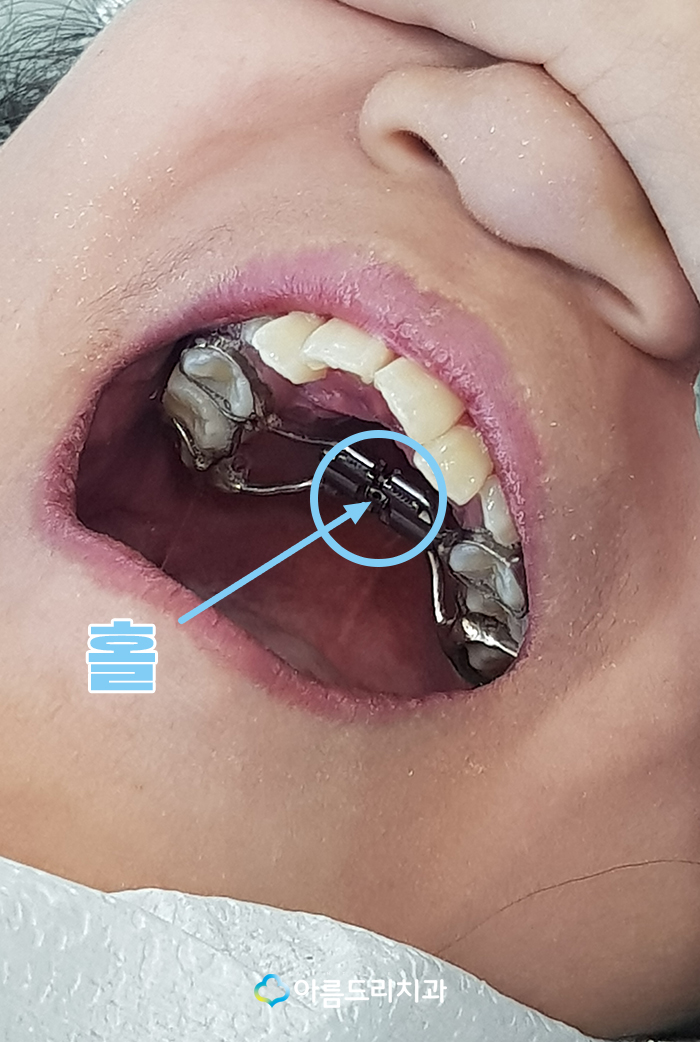

하은이에게 꼭 맞는 맞춤형으로 제작된

악궁확장장치의 가운데를 보시면 홀이

있는 것을 확인 하실 수 있습니다.

아래에 있는 사진의 장비로 의료진이

이야기 해주는 기간에(하루에 한번, 3일에

한번, 일주일에 한번) 맞게 홀에 끼워 돌려

주시면 장치의 가운데 부분이 벌어지면서

악궁의 악궁이 넓어지게 되는 원리입니다.